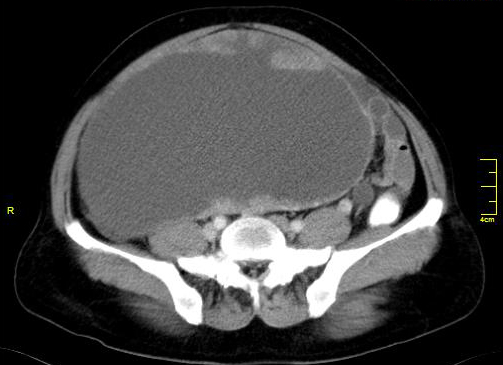

Stage 4: distant metastases, pleural effusion, pleural nodules or focal thickening suggest this stage. Accuracy for detecting peritoneal deposits is dependent on their location, size and presence of ascites. MRI and CT have similar sensitivity in detection of peritoneal deposits greater than 1cm. Peritoneal deposits appear has rounded, cake like, stellate or ill-defined masses. However deposits in mesentery/ implant on surface of bowel and calcified deposits are better seen in CT. Adjacent pelvic organ involvement may be difficult to diagnose accurately. In large ovarian tumour, it may be difficult to identify uterus which is partially or completely surrounded by tumour. Pelvic side wall invasion is suspected when tumour lies within 3mm of pelvic side wall or when iliac vessel are surrounded or displaced by tumour. Focal obliteration of fat plane or tumour encasement of bladder or recto sigmoid is highly suspicious of involvement of the structures. Staging accuracy is 80-90% (Figures 9 & 10).

Figure 10: Omental caking with carcinoma of the ovary.